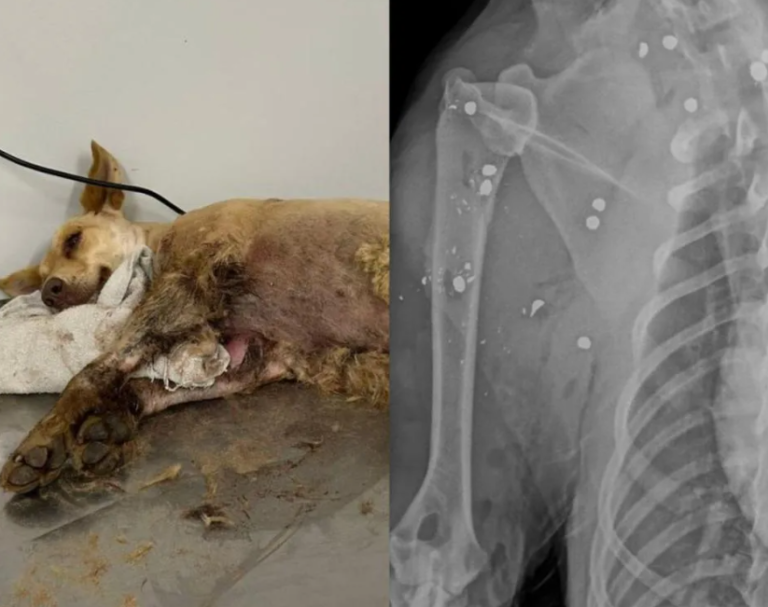

Next: Cachorra sobrevive após ser atingida por mais de 20 chumbinhos em Gaspar.